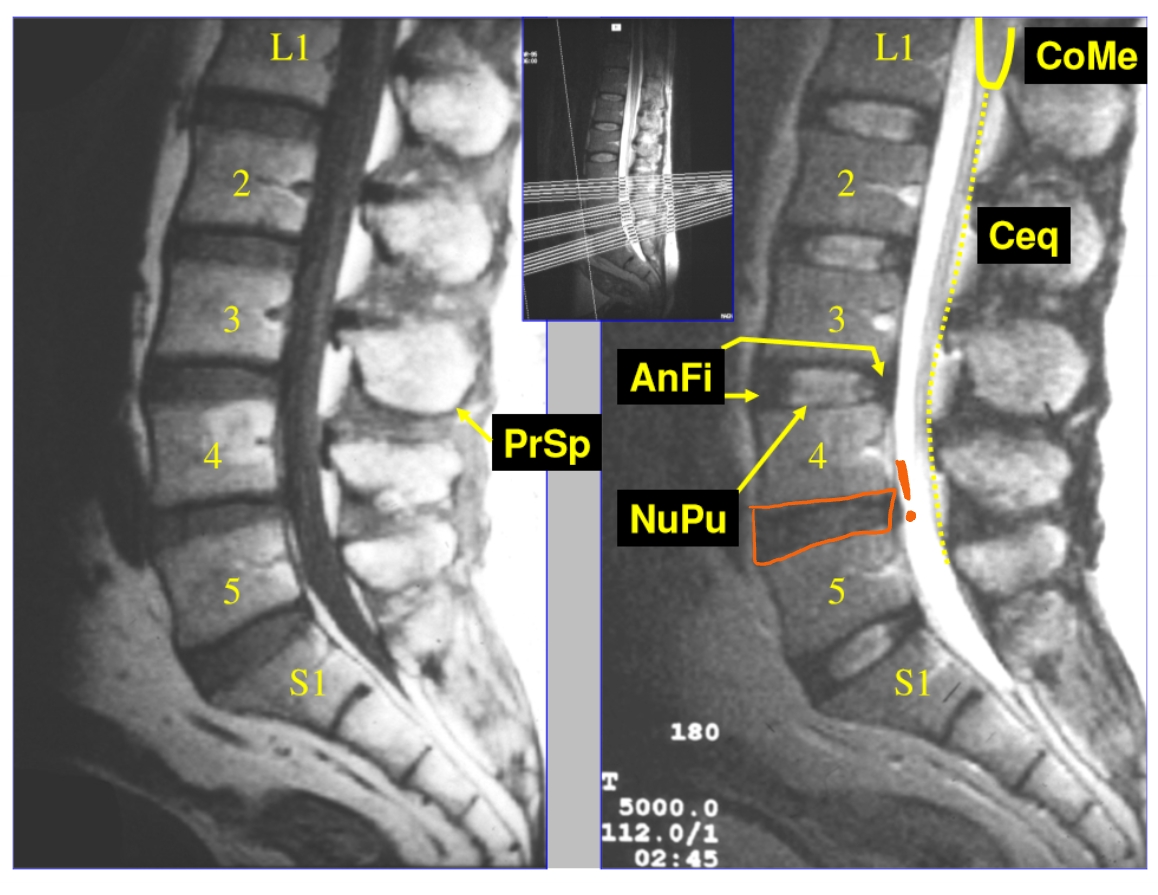

MRI

= magnetische resonantie

werkt met magneetvelden & radiogolven → dus niet met röntgenstralen

2 soorten MRI-beelden

T1-beeld

water & CSV (cerebrospinaal vocht) = donkergrijs

T2-beeld

water (en CSV) = wit

→ beeld in het mediosagittaal vlak

cervicale lordose

thoracale kyphose

lumbale lordose

annulus fibrosus

buitenste vezels

vangt de krachten op

nucleus pulposus

enige wat nog overblijft van de embryologische chorda

CT-scan: sagittaal & parasagittal

(medio)sagittaal = door het midden

parasagittaal = een beetje naar links of naar rechts

conus medullaris

cauda equina (= paardenstaart)

nucleus pulposus

annulus fibrosus

→ MRI: T2-beeld

discus is donker in het midden = uitgedroogd

begint te verslijten → 1e stadium van degeneratief discuslijden